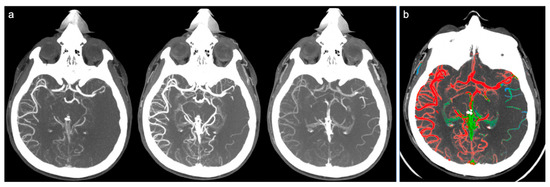

Figure 1.

Example of good collateral circulation at ColorViz. (a) mCTA shows a right-sided M1 segment occlusion with good pial artery filling (1 phase delay); (b) ColorViz map shows predominant red vessels in the affected territory downstream from the occlusion (score of 3).